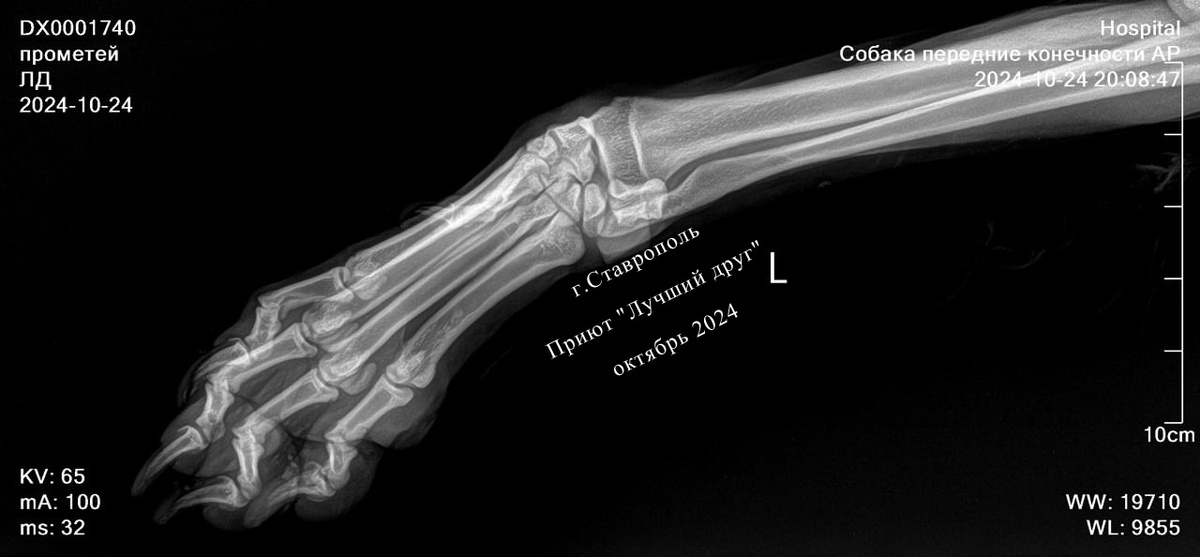

Пёс, который родился в рубашке. Помогите Прометею, попавшему в беду!

Потому что после столкновения с машиной, несущейся на большой скорости, собаки остаются лежать на дороге с переломами в лучшем случае, а в худшем упокоятся навсегда. Прометей вышел из ДТП относительно целым, по рентгену кости целые, есть рваные раны по телу, большая рана в области запястья. Предположительно, до встречи с машиной его вдобавок покусали сородичи за какие-то проделки, он от болевого шока метнулся в сторону и попал под колеса.

Потому что после столкновения с машиной, несущейся на большой скорости, собаки остаются лежать на дороге с переломами в лучшем случае, а в худшем упокоятся навсегда. Прометей вышел из ДТП относительно целым, по рентгену кости целые, есть рваные раны по телу, большая рана в области запястья.